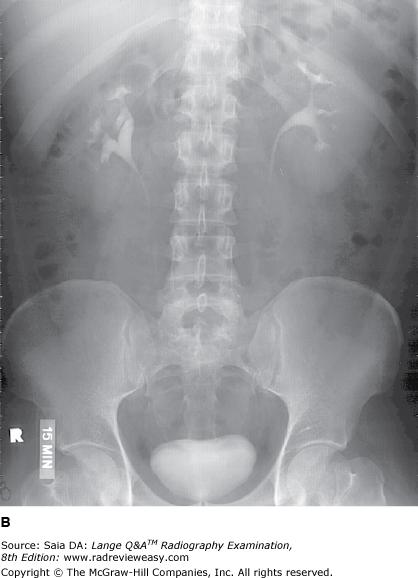

The number 1 in the radiograph in Figure A represents which of the following renal structures?

B Renal pelvis

-The pictured radiograph is one of a series of IVU (IU) images. It was done prone at 20 minutes after injection of the contrast medium. The urinary collecting system is well demonstrated. The renal pelvis(number 1) is the proximal expanded end of the ureter lying within the renal sinus. The minor calyces(number 3) receive urine from the collecting tubules of the renal pyramids and convey it to the major calyces (number 2), which empty into the renal pelvis. Urine is carried down the ureters by peristaltic waves.